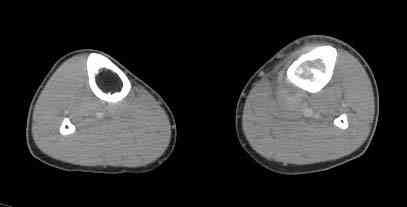

При обращении к нам произведена сцинтиграфия скелета - зоны гиперфиксации РФП: верхняя треть голени- 960%, нижняя треть бедра - 380%, Дистальный метафиз голени и затылочная область - 140%. В легких - метастазов нет. Произведена КТ (картинки в приложении). Учитывая абсолютную нестыковку рентгенологических и морфологических данных повторно биопсия. Выявлено, что первичная биопсия выполнялась из поверхностной параоссальной зоны - там локализованы хрящеподобные массы, далее очень плотная кость без хрящевых участков - биоптат взят фрезой с большим трудом. Морфологического заключения пока нет. Хотелось бы узнать Ваши варианты диагноза и соответственно тактику.